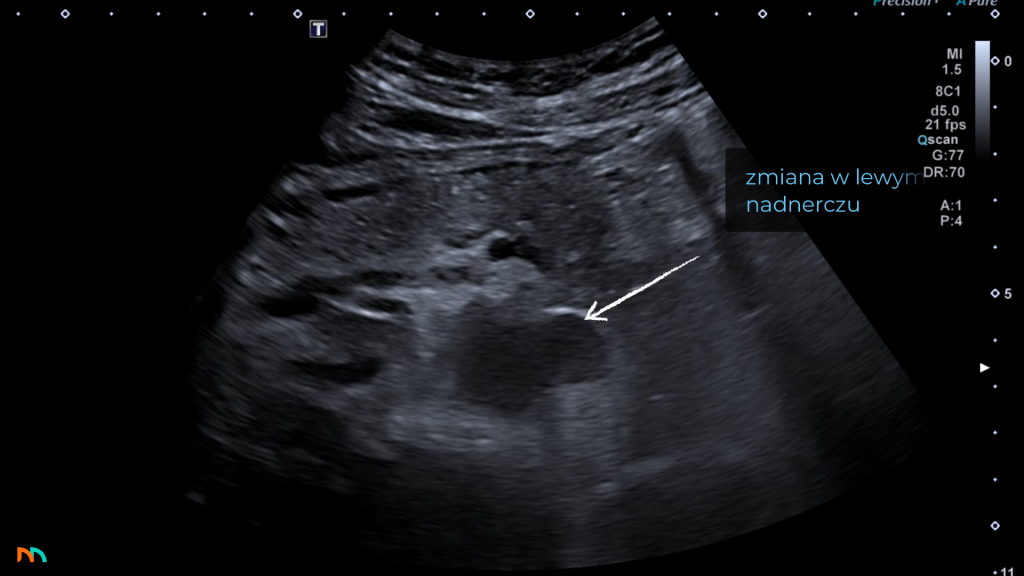

Po stronie lewej sytuacja jest nieco bardziej, z punktu widzenia ultrasonografii, złożona. Samo położenie pola nadnerczowego jest podobne jak po stronie prawej, szukamy go dogłowowo, do przodu i przyśrodkowo w stosunku do bieguna górnego nerki lewej. Niestety w tej lokalizacji nie mamy okna akustycznego w postaci wątroby, a żołądek oraz zagięcie śledzionowe okrężnicy, które często skutecznie ten obszar przesłaniają. Mimo to w badaniu nie powinniśmy pomijać tej okolicy. W związku z trudniejszymi warunkami insonacji stwierdzamy zmiany nadnercza lewego, dopiero gdy osiągną odpowiedni kaliber, w praktyce jest to średnica 20-30mm. Zdarza się, że zmian ogniskowych lewego nadnercza nie jesteśmy w stanie zobrazować, nawet wiedząc o ich obecności z innych badań obrazowych.